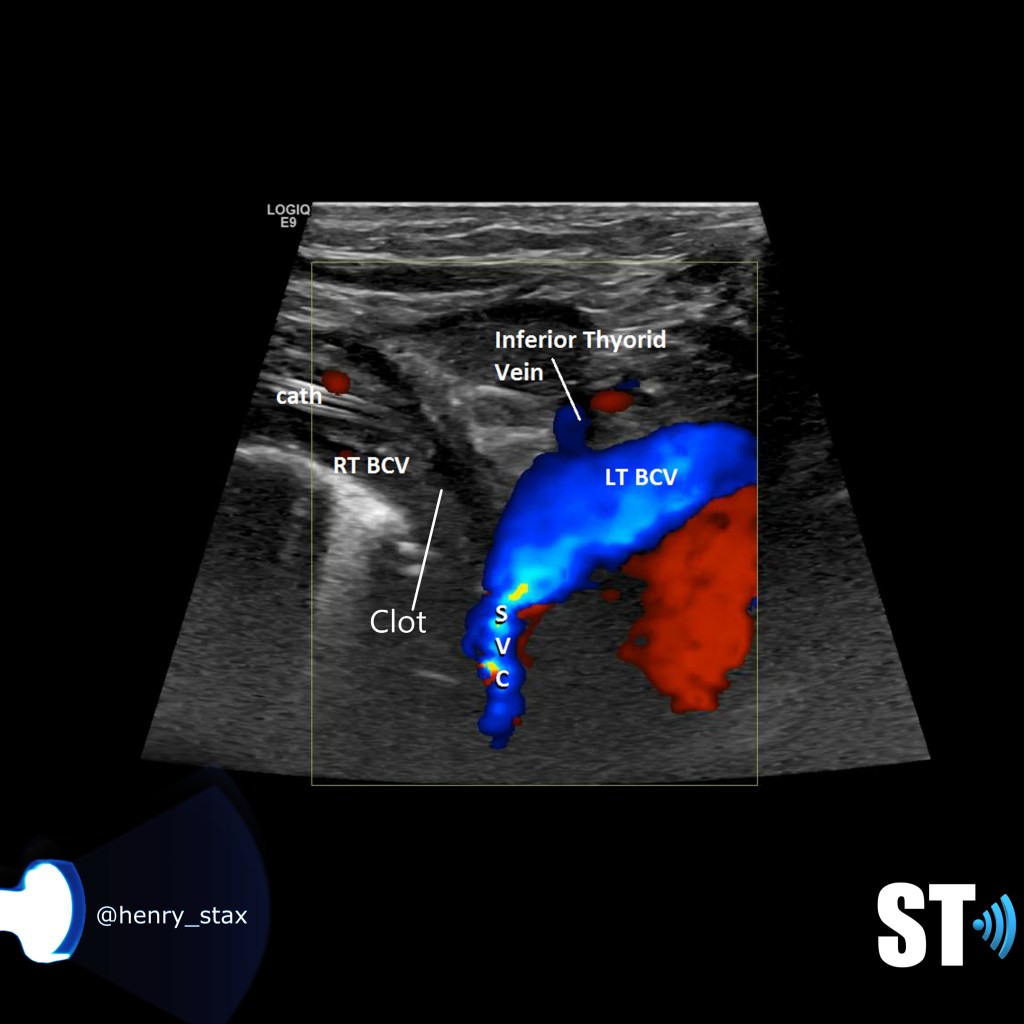

Thrombosis of the right innominate vessel with indwelling catheter